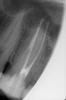

круговерть Опубликовано 12 июля, 2011 Автор Поделиться Опубликовано 12 июля, 2011 прилагаю снимок, не могли бы вы оценить качество пломбировки каналов? постоянно пью обезбол., т.к. зуб продолжает болетьhttp://i012.radikal.ru/1107/97/1d19e55bb9cft.jpg Ссылка на комментарий

Scrabble Опубликовано 12 июля, 2011 Поделиться Опубликовано 12 июля, 2011 В одном канале выведено за верхушку. Ссылка на комментарий

круговерть Опубликовано 13 июля, 2011 Автор Поделиться Опубликовано 13 июля, 2011 (изменено) В одном канале выведено за верхушку.спасибо за ответ!я не совсем понимаю, что это значит и чем чревато?(((( перелечивать? т.к. стандарт оказания помощи допускает возможность небольшого выведения пломбировочного материала за верхушку корня, Вы бы что посоветовали, видя мой снимок?существует ли вероятнсть(или это нельзя предвидеть?)выведения пломбировочного материалов в гайморову пазуху ?(( Изменено 13 июля, 2011 пользователем круговерть Ссылка на комментарий

Scrabble Опубликовано 13 июля, 2011 Поделиться Опубликовано 13 июля, 2011 Так скажем, исключить эту вероятность можно только после КТ. Гуттаперчу из-за верхушки уже не вынуть. Ссылка на комментарий